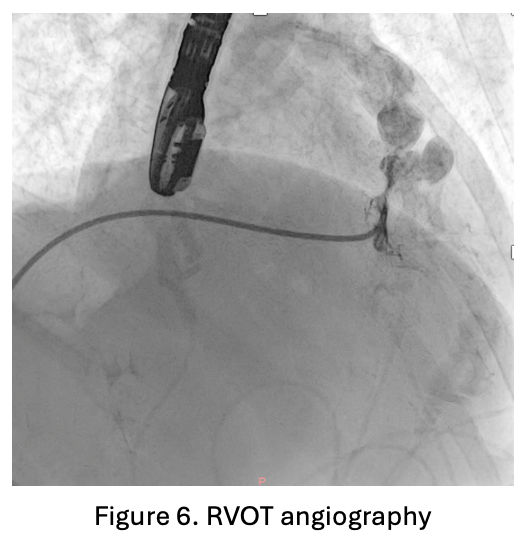

An 8F sheath was inserted into the femoral vein and an arterial line was placed in the femoral artery. Intraoperative transesophageal echocardiography (TOE) showed a very tight right ventricular outflow tract (RVOT) measuring 23.7 mm in length, with a left ventricular ejection fraction (LVEF) of 51.7% by Simpson¡¯s method. RVOT angiography performed using a 3.5/5F Guiding JR catheter confirmed narrowing at the RVOT segment.